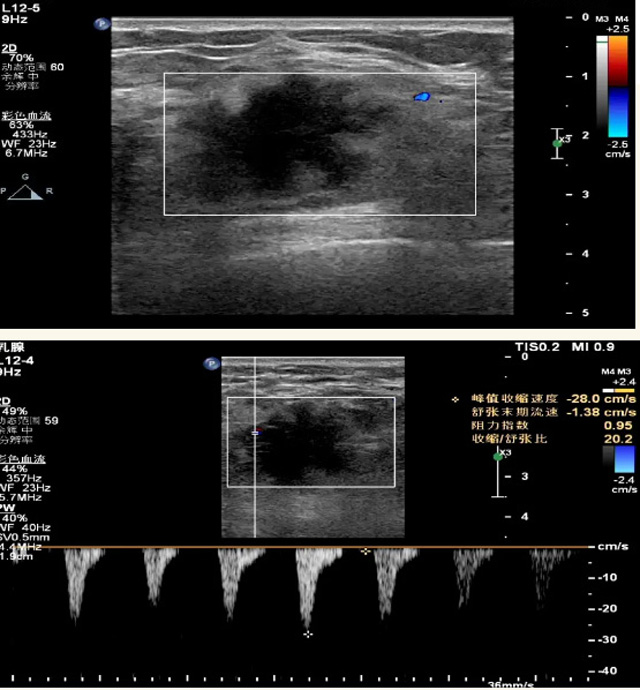

乳腺B超檢查無(wú)輻射,對(duì)囊性病變敏感,可以實(shí)時(shí)觀察病灶。超聲引導(dǎo)活檢跟手術(shù)前的定位。就是它對(duì)于微小的鈣化查出率比鉬靶稍微差點(diǎn)。磁共振MRI檢查也是是沒(méi)有輻射的,對(duì)備孕跟已經(jīng)懷孕的人士比較友好。不用擔(dān)心這個(gè)輻射影響胎兒?jiǎn)栴}。對(duì)乳腺病灶敏感性較高,致密乳腺病灶、乳腺癌的復(fù)發(fā),準(zhǔn)確鑒別囊性及實(shí)性病變??梢詭椭R床醫(yī)生判斷惡性、良性病變。但是MRI磁共振對(duì)微小鈣化不明顯,微鈣化還是鉬靶靠譜點(diǎn)。檢查時(shí)間比較長(zhǎng),有偽影的影響。費(fèi)用相對(duì)B超,鉬靶高很多。

乳腺B超